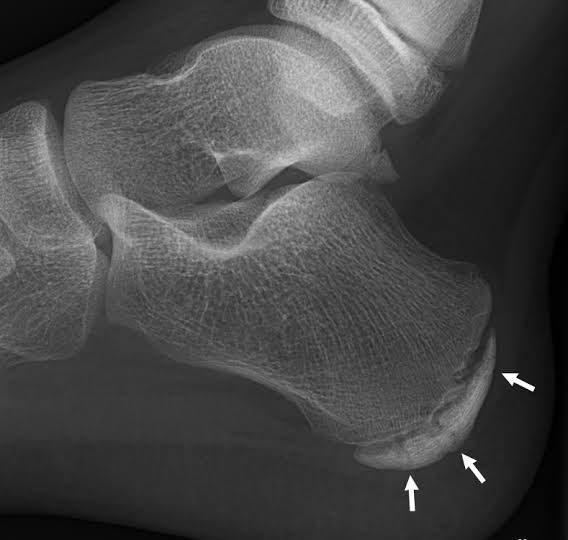

Sever's disease is a painful condition of the heel that occurs in growing children. It happens when the tendon that attaches to the back of the heel (the Achilles tendon) pulls on the growth plate (the apophysis) of the bone of the heel (the calcaneus).